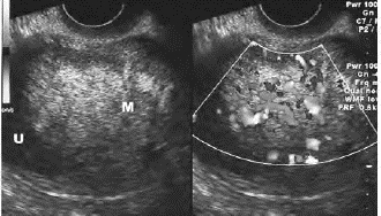

1.37.7七、卵巢囊性肿瘤

-